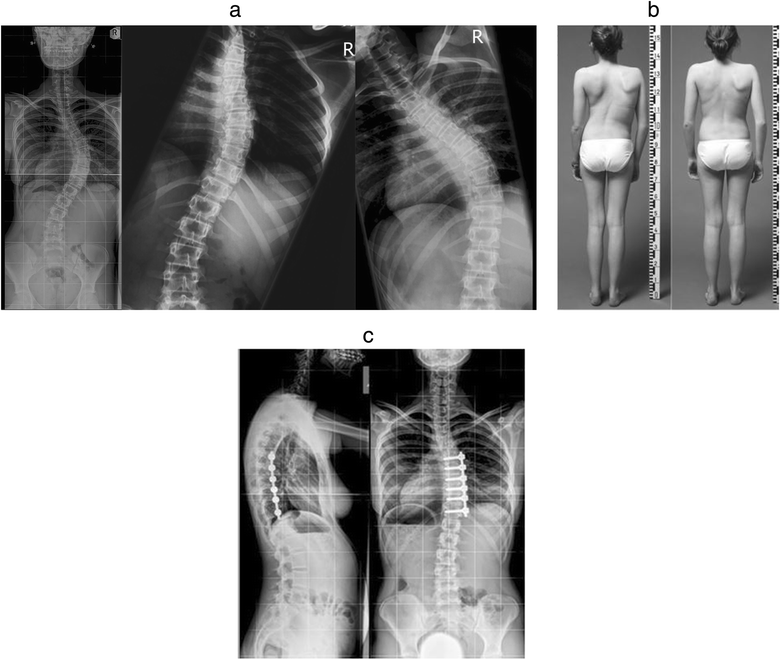

From www.researchgate.net

Case example of an adolescent idiopathic scoliosis patient with... Download Scientific Diagram Lumbar Curve Adolescent Idiopathic Scoliosis the management of adolescent idiopathic scoliosis depends on the severity of the scoliosis. adolescent idiopathic scoliosis (ais) represents the most. adolescent idiopathic scoliosis is a coronal plane spinal deformity which most commonly presents in adolescent. idiopathic scoliosis curves vary in size, and mild curves are more common than larger curves. adolescent idiopathic scoliosis is a. Lumbar Curve Adolescent Idiopathic Scoliosis.